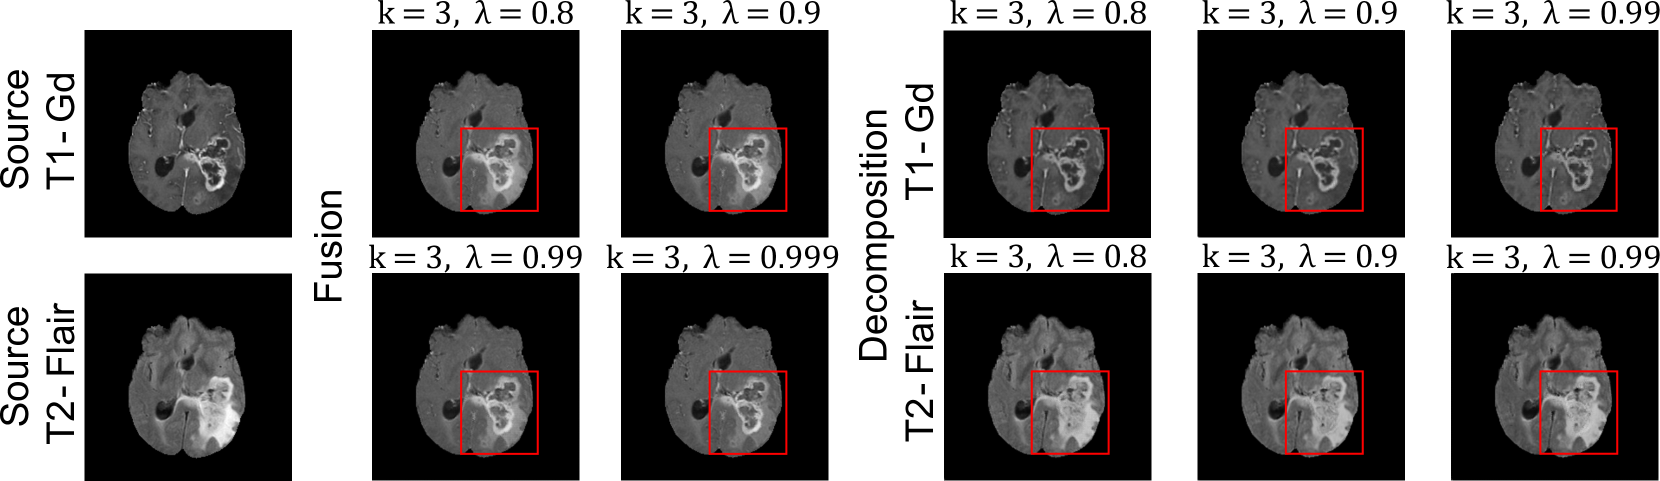

Refer to caption

Figure 4: Qualitative results of our FusionINN model at α=0.5𝛼0.5\alpha=0.5italic_α = 0.5 and z𝒩(0,I)similar-to𝑧𝒩0𝐼z\sim\mathcal{N}(0,I)italic_z ∼ caligraphic_N ( 0 , italic_I ).

Table 2 demonstrates the impact of various parameters on FusionINN’s fusion and decomposition performance. The results indicate that three coupling blocks with λ=0.8𝜆0.8\lambda=0.8italic_λ = 0.8 and α=0.5𝛼0.5\alpha=0.5italic_α = 0.5 produce competitive results in terms of QSSIMsubscript𝑄𝑆𝑆𝐼𝑀Q_{SSIM}italic_Q start_POSTSUBSCRIPT italic_S italic_S italic_I italic_M end_POSTSUBSCRIPT scores. Additionally, increasing α𝛼\alphaitalic_α enhances image fusion performance with respect to at least one source modality. We also explored different latent priors for z𝑧zitalic_z, including learning zeros, ones and uniform distribution 𝒰[0,1)𝒰01\mathcal{U}[0,1)caligraphic_U [ 0 , 1 ). The results show that a normally distributed z𝑧zitalic_z outperforms other settings, as it might contain more information about the data distribution than, for example, an image containing only zeros. In Fig. 4, the qualitative fusion and decomposition results convey that both λ=0.8𝜆0.8\lambda=0.8italic_λ = 0.8 and 0.90.90.90.9 prevents under-compensation of QSSIMsubscript𝑄𝑆𝑆𝐼𝑀Q_{SSIM}italic_Q start_POSTSUBSCRIPT italic_S italic_S italic_I italic_M end_POSTSUBSCRIPT via 2subscript2\ell_{2}roman_ℓ start_POSTSUBSCRIPT 2 end_POSTSUBSCRIPT loss, resulting in superior visual quality.